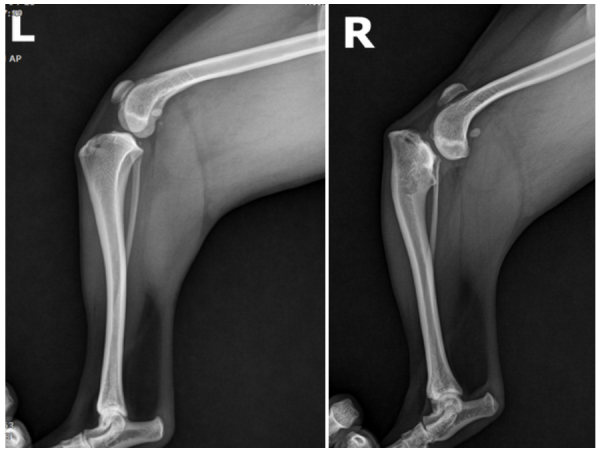

위에 사진에서 뒷다리의 무릎 아래쪽에 있는 길다란 뼈가 바로 경골입니다.

경골의 형태는 정상적으로 위의 사진과 같은 형태로 보여집니다.

왼쪽 다리에 비해 오른쪽 다리는

강아지 경골 뒤쪽 부분이 눈에 띄게 기울어져 있는 것이 보입니다.

이렇게 뼈의 각도가 심하게 틀어져 있으면 다리가 곧게 펴지지 않을 뿐 아니라

무릎 관절과 십자인대에 가해지는 부담이 커져

통증이 지속적으로 생길 수 있습니다.